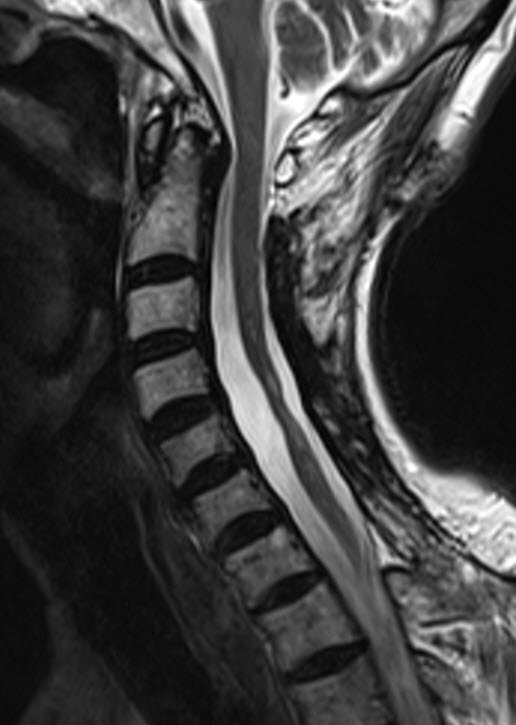

17-SEPTEMBER-1999 ALI MAHDI AWAD 50 YEARS INTRASPINAL

EPENDYMOMA EXTENDING FROM C2 DOWN TO C6. |